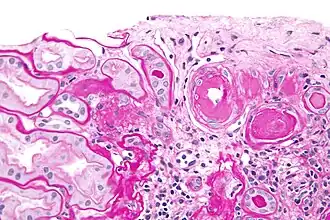

Micrografia do tecido de um rim estruturas arteriais hialinas (arteriolosclerose hialina).